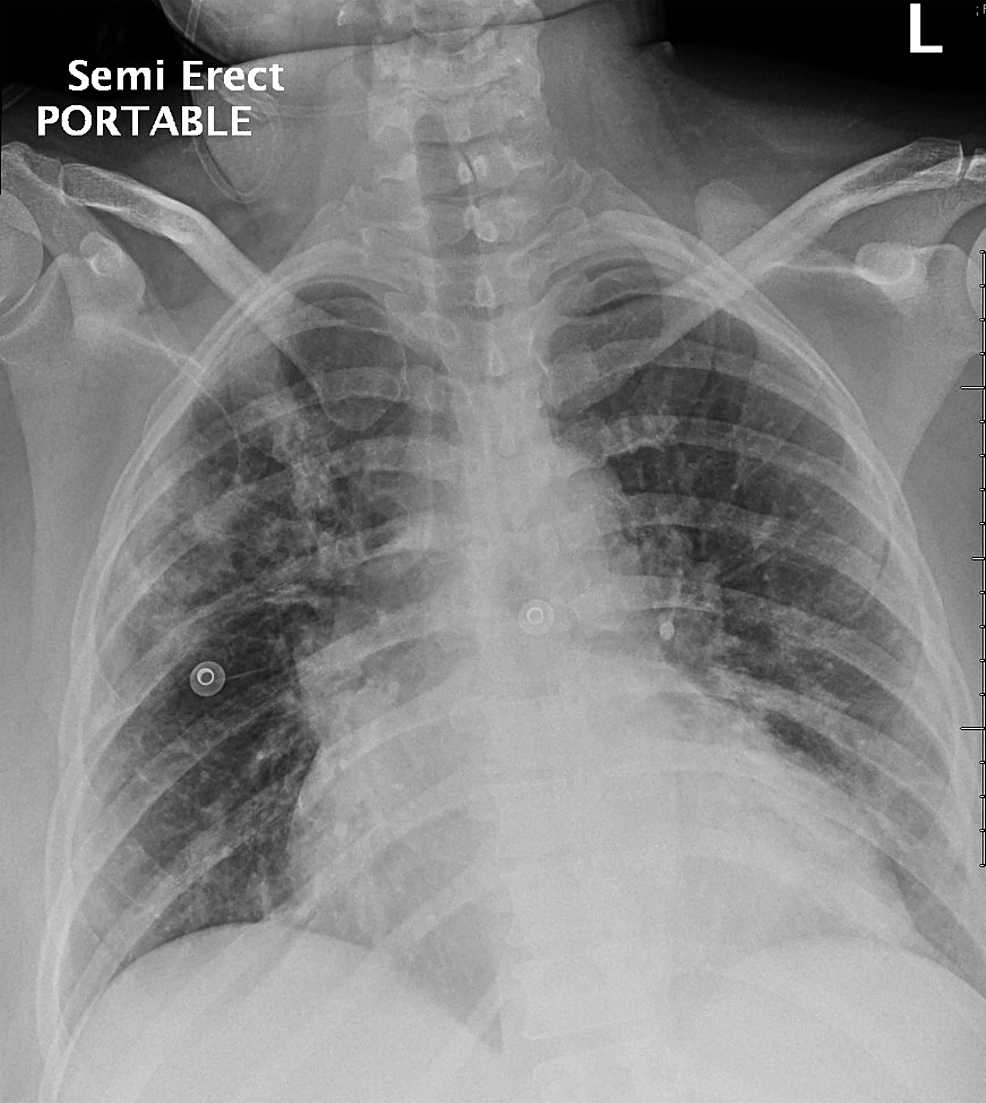

Does A Chest X Ray Show Myocarditis .   myocarditis can lead to heart failure, rhythm disturbances, or rarely cardiogenic shock (a condition that occurs when your heart suddenly cannot pump. A normal ecg does not exclude myocarditis.   these cells release chemicals.   chest pain may occur, in a variety of typical and atypical presentations. Occasionally a heart, or myocardial biopsy is. Will often be normal in myocarditis, but it may show features consistent with heart failure (alveolar oedema, bilateral pleural effusions,.

Occasionally a heart, or myocardial biopsy is.   these cells release chemicals. A normal ecg does not exclude myocarditis.   chest pain may occur, in a variety of typical and atypical presentations.   myocarditis can lead to heart failure, rhythm disturbances, or rarely cardiogenic shock (a condition that occurs when your heart suddenly cannot pump. Will often be normal in myocarditis, but it may show features consistent with heart failure (alveolar oedema, bilateral pleural effusions,.